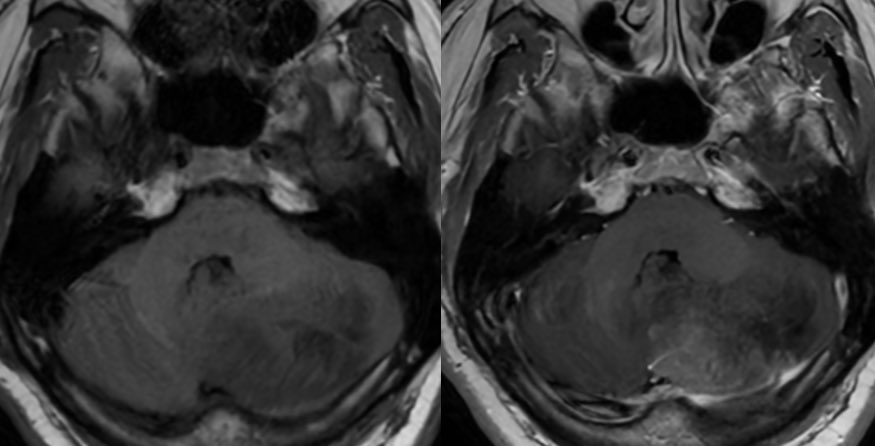

🔷Imaging:

💡 Hypercellular tumor so DENSE on CT and DIFFUSION RESTRICTION (consistent feature)

▶️Round/lobulated morphology

▶️Hemorrhage is rare but calcifications seen in ~20%

💡 Most medulloblastomas enhance except group 4 which may have minimal to no enhancement

💡 Both Lhermitte-Duclos & Medulloblastoma SHH can have a striated appearance! Use DWI/ADC, density on CT, & enhancement to distinguish!